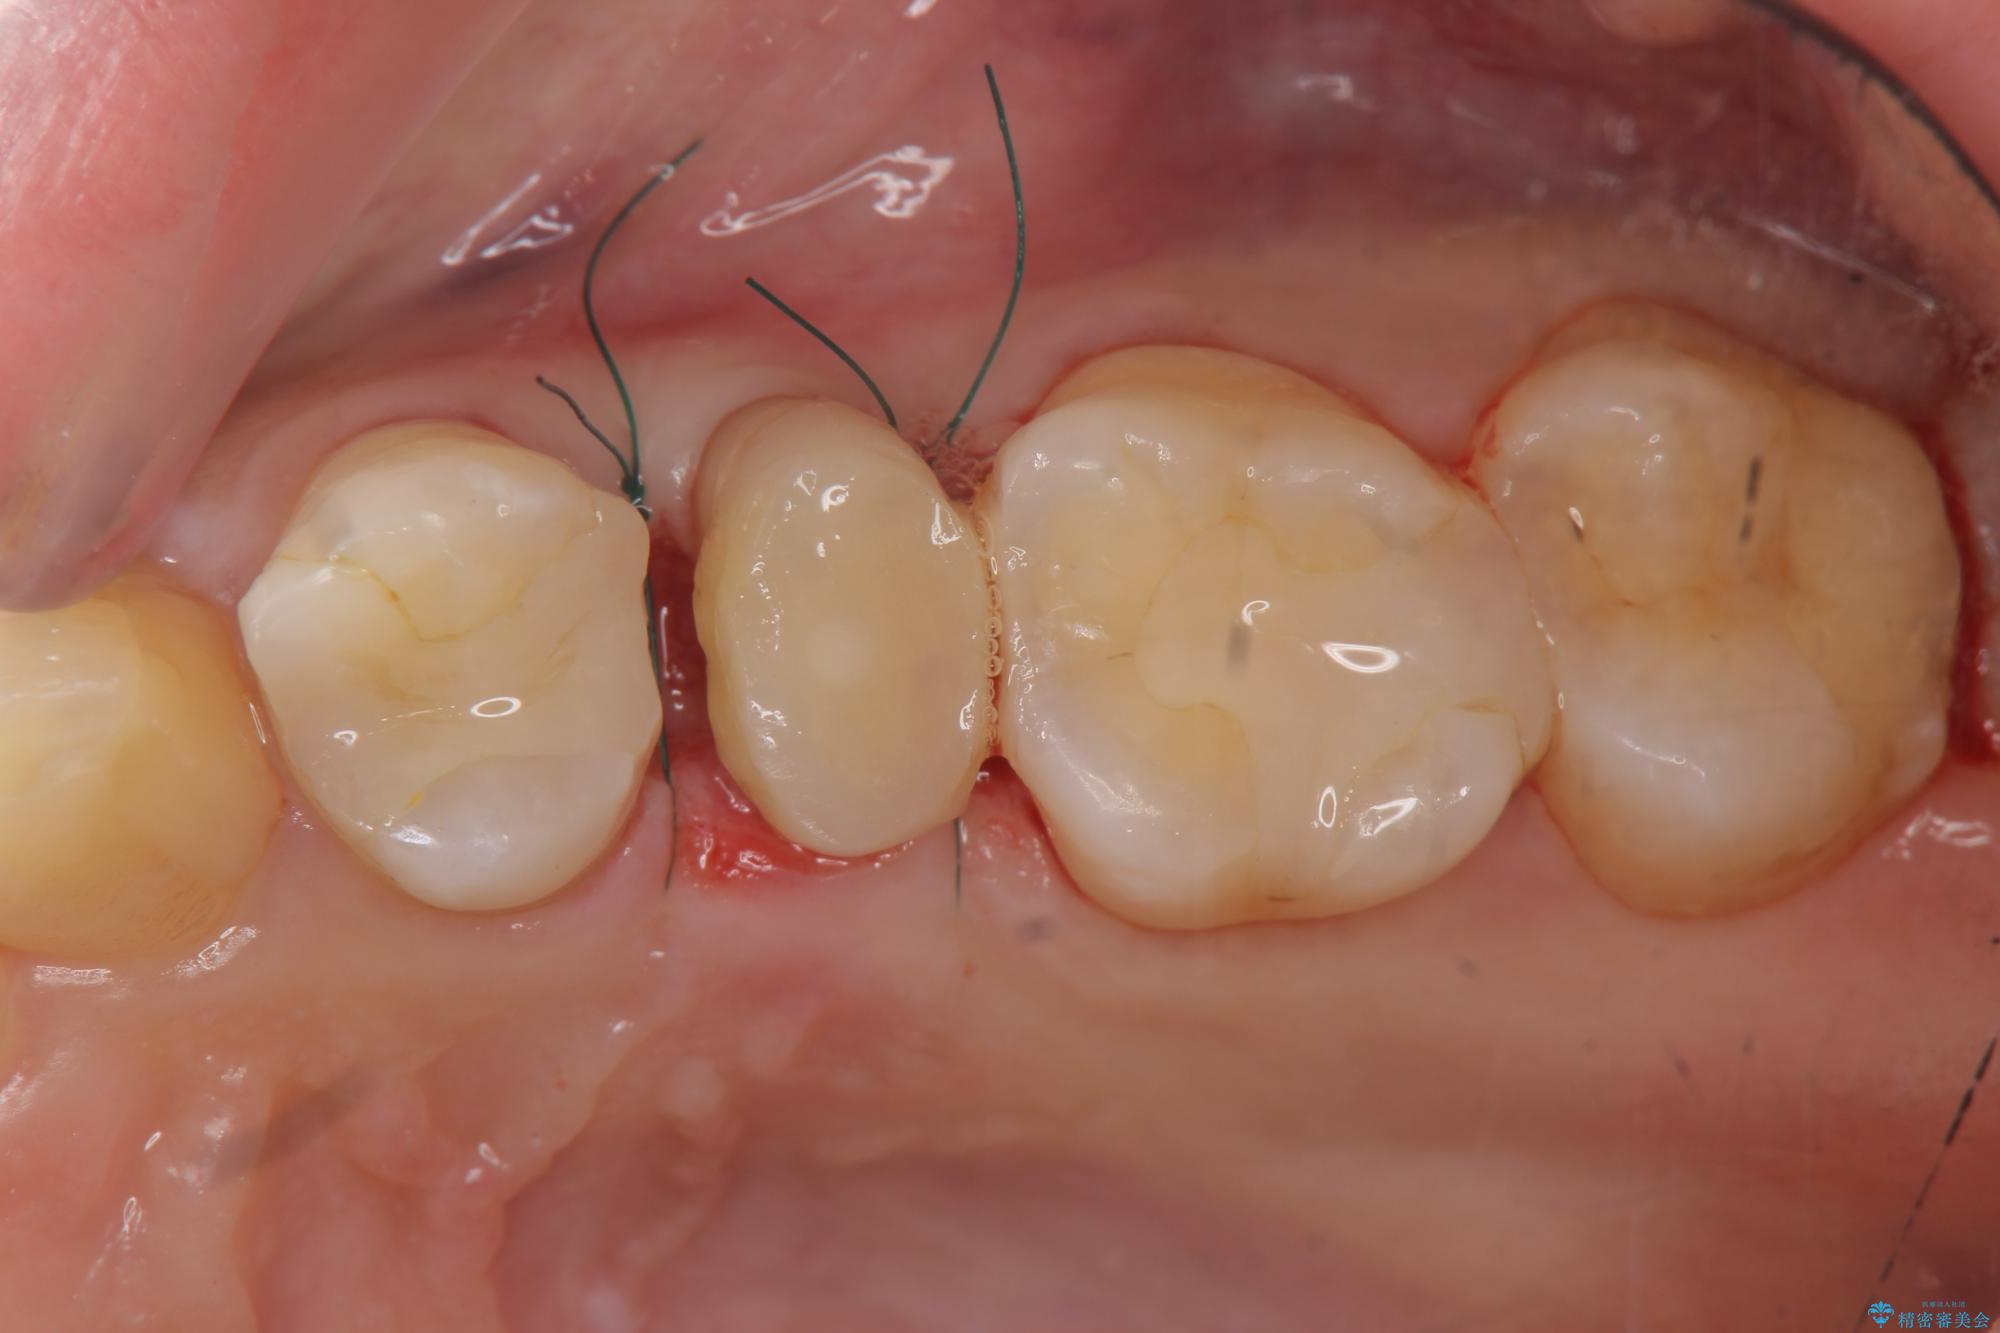

- 歯ぐきの腫れや、歯の内部が黒く見えることからの虫歯の治療を求めて来院されました。

虫歯が大きかったことから、神経の温存はできたものの歯ぐきよりも深い虫歯の問題を解決するため部分矯正治療を併用したセラミック治療を行うこととしました。

- 50.6万円(ジルコニアクラウン×3・仮歯×3・部分矯正)費用は治療当時の料金となります

当初、歯ぐきよりも深い虫歯のぞんざいや、歯のポジションに問題がありましたがマルチブラケットを用いた部分矯正を行うことで適切な位置へと歯を移動させ、歯周環境を整えたセラミック治療を行うことができました。